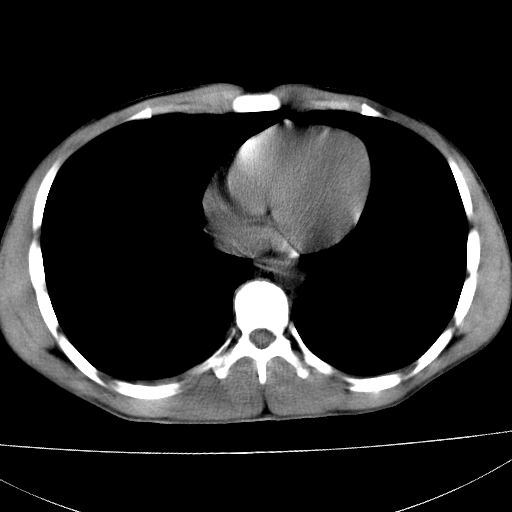

标题: CT15860:男,21岁,腹部外伤2小时伴胸疼。 [打印本页]

标题: CT15860:男,21岁,腹部外伤2小时伴胸疼。

b超示:肝破裂。

肝脏及肾脏明显有损伤性改变并激发腹腔内积液(血),以肝脏撕裂及肾周积血显著。

1)肝破裂伴腹腔积液(血)。2)右肾破裂伴右肾包膜下及肾周血肿。3)腹部空腔脏器穿孔可能。4)右侧少量胸腔积液(血)。

1)肝破裂伴腹腔积液(血)。2)右肾破裂伴右肾包膜下及肾周血肿。3)右侧少量胸腔积液(血)。

1肝挫伤伴腹腔积液。2右肾挫裂伤伴右肾包膜及肾后间隙肿血肿。3右肾脏周围的积气,十二指肠显示结构不清,考虑十二指肠降部破裂可能性大。